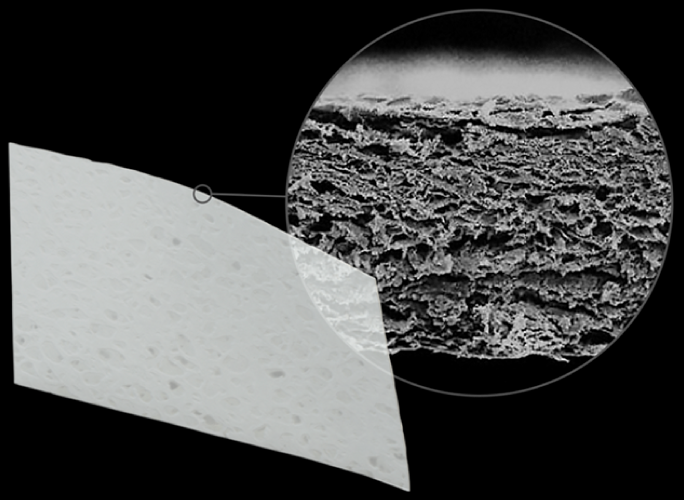

OssGuide is an absorbable dental membrane for guided bone regeneration

made of purified collagen without cross-linking or chemical treatment.

OssGuide is an absorbable dental membrane for guided bone regeneration

made of purified collagen without cross-linking or chemical treatment.

Better Stability

OssGuide functions as barrier to provide the prolonged

space maintenance with the long resorption period.

OssGuide is biodegradable and absorbed

within 24 weeks after implantation.

Better Tissue Integration

OssGuide has high porosity and specific surface area,

which support excellent blood supply.

This ensures optimal regeneration of bone and soft tissue.

Better Stability

OssGuide functions as barrier to provide the prolonged

space maintenance with the long resorption period.

OssGuide is biodegradable and absorbed

within 24 weeks after implantation.

Better Tissue Integration

OssGuide has high porosity and specific surface area,

which support excellent blood supply.

This ensures optimal regeneration of bone and soft tissue.